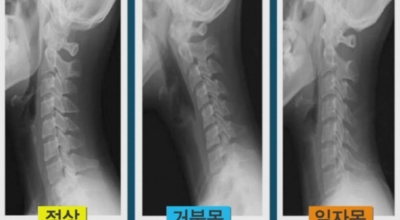

우리의 성인 기준 머리 무게는 약 5.5kg 정도이죠. 목을 앞으로 숙이는 잘못된 자세를 오랫동안 지속하다 보면 목 디스크 증상 발생의 원인이 돼요. 스마트폰의 장시간 사용하기 때문에 많이 발생되고 또 직업병으로 컴퓨터를 오래동안 사용하기 때문에 목뼈의 C자형이 변해서 거북목처럼 변형되기도 해요.